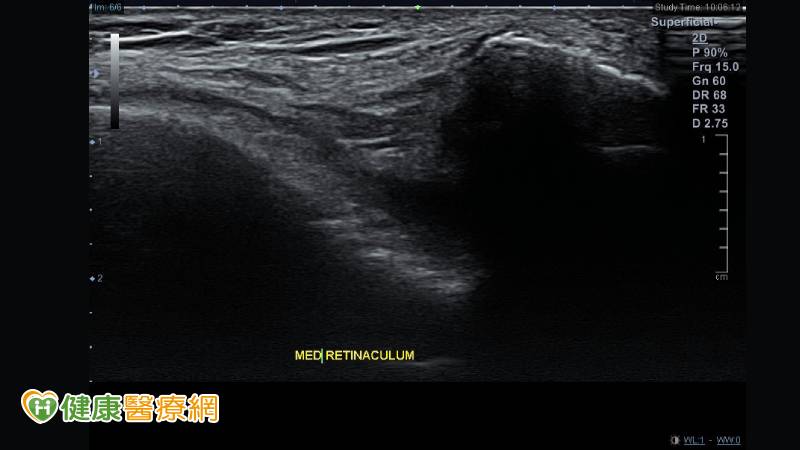

髕骨股骨疼痛症候群的患者常會有跑步時覺得膝蓋內外側的疼痛,或是蹲下站起時膝蓋卡卡或疼痛、膝關節僵硬腫脹、膝蓋彎曲時常有喀啦聲響。針對髕骨股骨疼痛症候群的檢查及診斷,可以藉由病史及理學檢查評估疼痛及受損部位,必要時並配合X光檢查髕骨外翻的程度(圖一)、超音波檢查內外髕支持帶有無受損(圖二)、核磁共振檢查髕骨下的軟骨有無受損情形。

▲(圖二)超音波檢查內外髕支持帶有無受損